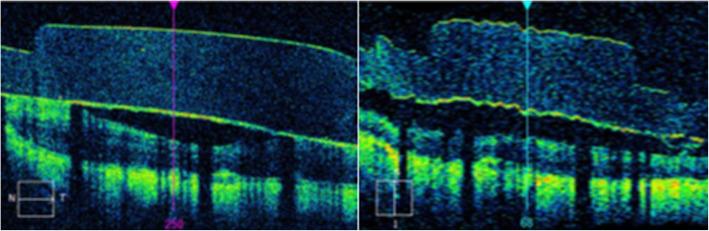

Five patients with implantation of the Argus II Retinal Prosthesis were enrolled in this single-institution retrospective study. Patient demographics were collected from medical records. Visual function data (Square Localization [SL] and Direction of Motion [DOM]) and Optical Coherence Tomography (Cirrus HD-OCT) images were extracted retrospectively from the Argus II Retinal Prosthesis Post-Approval study. Visual function tests were performed with the device OFF and ON at each study visit. Electrode array-retina gap distances were measured at each of the array's 60 electrodes using the Cirrus HD-OCT software in both the nasotemporal and superoinferior planes. Data was obtained at baseline, and post-operative month 1, month 3, month 6, and year 1. Sensitivity detection thresholds were obtained at the initial programming visit and each reprogramming session.

本研究为单中心回顾性研究,纳入了 5 名植入 Argus II 视网膜假体的患者。从病历中收集患者的人口统计学资料。回顾性地从 Argus II 视网膜假体批准后研究中提取视觉功能数据(方形定位 [SL] 和运动方向 [DOM])和光学相干断层扫描(Cirrus HD-OCT)图像。在每次研究访视时,使用设备 OFF 和 ON 进行视觉功能测试。在 Cirrus HD-OCT 软件中,在鼻颞和上下平面上测量每个阵列的 60 个电极的电极阵列-视网膜间隙距离。在基线、术后第 1、3、6 个月和第 1 年获得数据。在初始编程访问和每次重新编程会话时获得敏感度检测阈值。